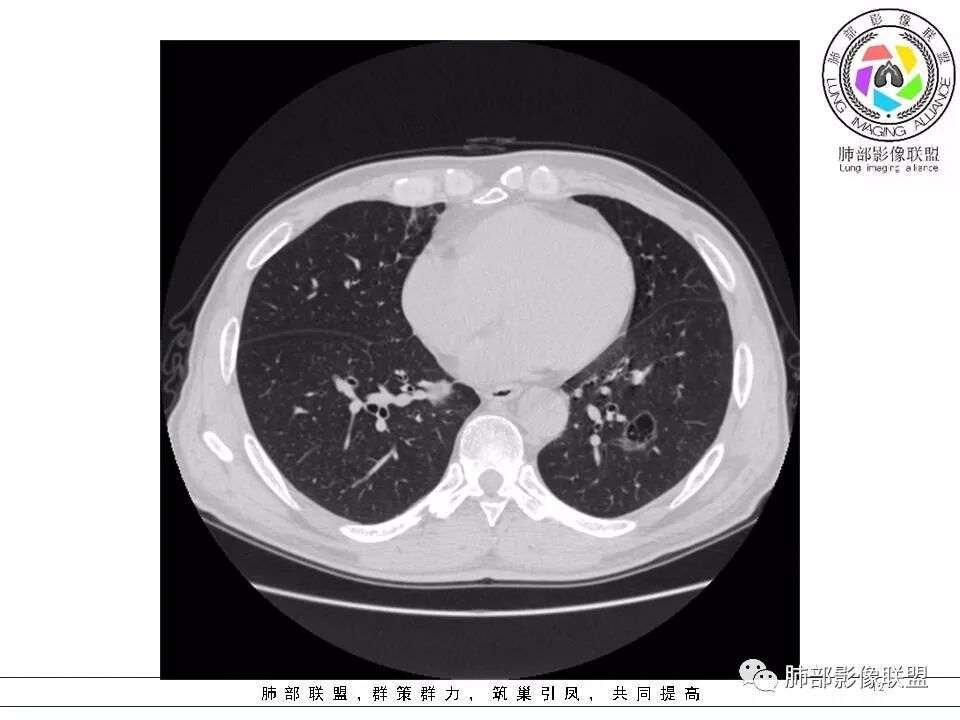

左肺下叶囊,壁厚薄不一,周围GG O,偏实,支气管进入ggo,不确定是否截断。囊腔内分隔。要考虑恶性。首次发现,需要复查一次观察其变化。鉴别霉菌

老年男性,左肺下叶囊腔,内有分隔,壁厚薄不均,偏后下方见支气管开口,壁增厚,局部见片状高密度影,临近囊壁外缘见磨玻璃影,部分界清晰。考虑1.感染,支气管与囊腔形成活瓣阻塞;2囊腔型腺癌,在抗炎治疗后复查无变化的情况下,直接切掉

左下肺囊腔病变,薄壁,内分隔,支气管进入,考支气管活瓣形成的囊腔,其旁血管旁见磨玻璃影,无糖尿病病史,抗炎无效,先考虑囊腔型腺癌,鉴别毛霉。

老年男性,左肺下叶外基底段囊腔,壁厚薄不均,周围可见磨玻璃影,腔内密度不均匀,可见索条及结节,考虑囊腔型肺癌,鉴别霉菌

53岁男性,间断发热半月余,肿瘤指标不高。CT:左下肺囊腔样病变,内见分隔及点状线条样影,壁偏心性增厚,下缘血管穿过并增粗,后方伴边缘清晰,磨玻璃影,边缘有轻度膨隆及分叶,支气管未见截断。考虑囊腔型腺癌可能性大。

磨玻璃成分,分割,囊,血管弯轻微,警惕囊腔型腺癌。

鉴别:囊腔鳞癌;

处理:找老片对照;手术。

53岁男性,间断发热半月。胸CT:左下叶囊腔性病变,外形边界不规则,周围有边界较清楚磨玻璃,囊内见分隔,囊壁厚薄不均,壁结节,内有小囊,血管集束。考虑:囊腔样腺癌?鉴别:肺大疱、CPAM、PLCH等。

2.左肺下叶外基底段囊腔样病灶,轮廓柔和,壁厚薄不均,见壁结节。内见分隔或脊状突起。腔内见血管穿行。

3.囊壁外环以磨玻璃影,边界较清楚。

1.囊腔壁厚薄不均,壁结节,内有分隔,其内有血管穿行,指向新生物。

2.临近有边界清楚磨玻璃影,指向腺癌。